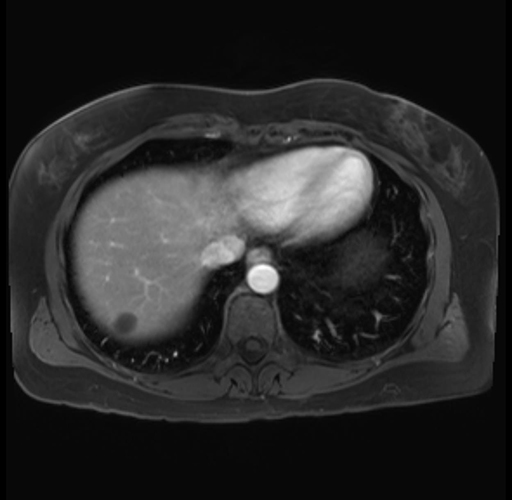

Imaging Analysis

Look through the patient's CT scan to identify any areas of concern for the necessary procedure.

Based on your CT findings, which issue(s) are present and would give reason for "planned slowing down moment(s)" in this case?

Considering a standard distal pancreatectomy procedure, what step(s) of the operation would you do differently in this case?